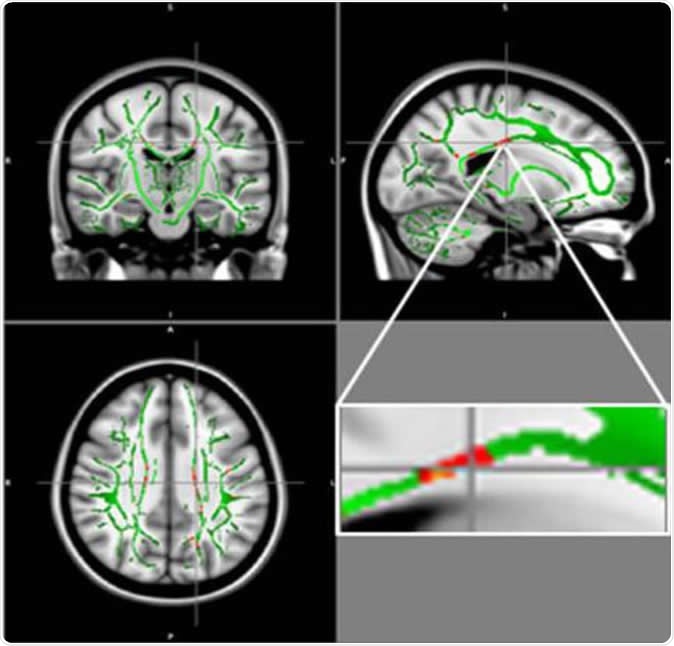

Reduction in fractional anisotropy (FA) in obese patients compared to the control group: At the intersection of the alignment vectors, a large cluster of FA decrease located in the corpus callosum on the left. In red: Reduction of FA in obese patients compared to controls, and FA skeleton (green), superimposed on the mean of FA images in sample.

The researchers performed DTI in about 60 healthy and 60 obese teenagers, between the ages of 12 and 16 years. They used the results to calculate a measure called fractional anisotropy (FA) that corresponds to the state of health of the white matter of the brain. The lower the FA value, the greater the damage in the white matter.

The study showed low FA values in obese teenagers in the area of the brain called the corpus callosum. This is the large bundle of white matter that links the two brain hemispheres and helps to coordinate all brain activity. Another area that showed low FA measurements was in the middle orbitofrontal gyrus, which is linked to emotional control and to reward pathways. These have been linked to addiction patterns of behaviour.